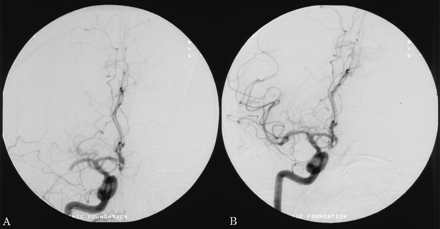

一个63岁的男人有权利M1大脑中动脉(MCA)闭塞后13天紧急冠状动脉旁路移植(CABG)对急性心肌梗死。心房扑动转换药物的前一天。他左半身不遂,视野受损的感觉在他的四肢。他最初的美国国立卫生研究院的中风尺度(署)得分是15。头部CT是正常的。被注入尿激酶200000台60分钟直接进入症状出现后血栓4小时。有良好的近端血管再通残余填充缺陷在某些M3分支(图1)。尽管国际标准化比率(INR) 1.4当天早些时候,重复INR立即过程是4.8之前完成。他得到10毫克维生素k IV肝素溶栓后开始2天。他开始他的左后立即手术。他只有一个提示视觉忽视在6周,是神经正常的病人在8个月。